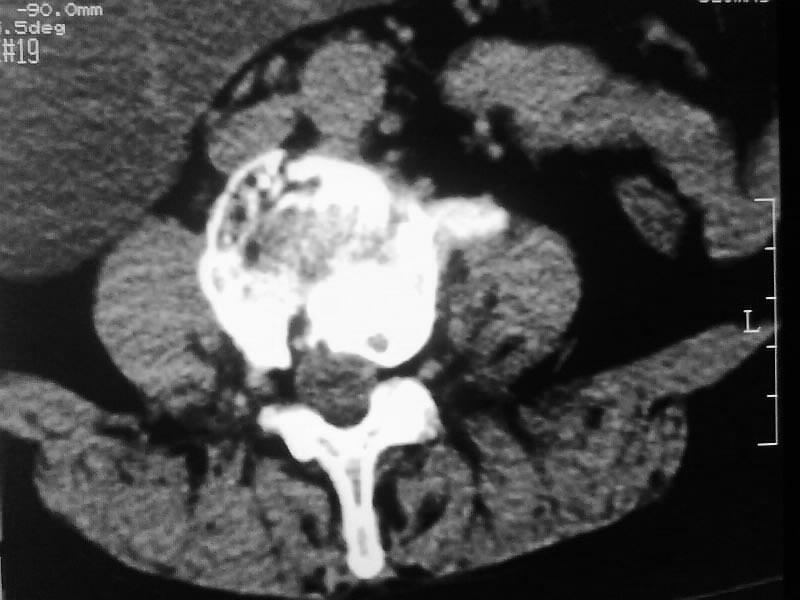

定位相示l2呈楔形改变(ct示陈旧性骨折改变,图像未传),l4.5椎体融合,以下是l4.5ct平扫.请各位看看,

考虑结核(有破坏、硬化及死骨)。

1、三四椎体结核,2、水平骶椎。

1、l1压缩性骨折(陈旧性)。

2、l3、4椎体结核。

就是腰1压缩性骨折,腰3\\4椎体结核(融合),水平骶椎.

支持 l1椎体陈旧性压缩性骨折;l3、4椎体结核(融合);水平骶椎。